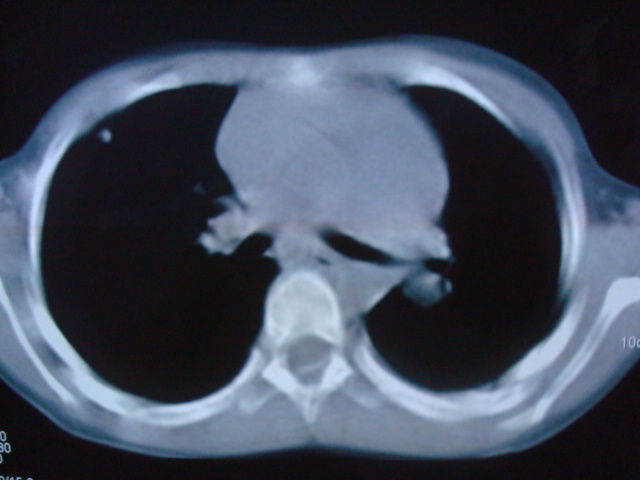

标题: PED0869:男,10岁,肺内多发结节+胸水

男,10岁,左胸痛,发热轻,血象高。后到省级权威医院治疗,病情明显好转,结果几天后公布。老机器,图像质量差,见谅。